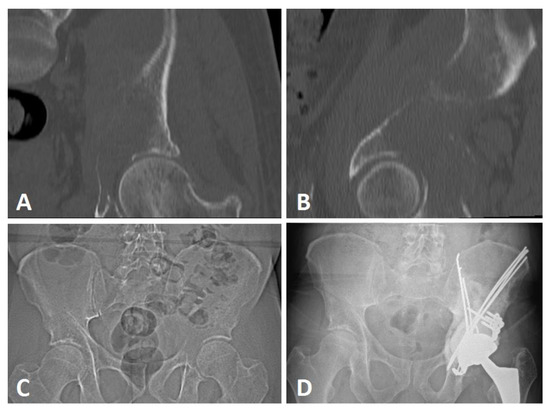

2.2. Extensive Acetabular Bone Loss Management

2.2.1. Treatment Strategy

2.2.2. Surgical Procedure

| Associated treatments | Radiation therapy | Preoperative | 8 (38.1%) |

| Postoperative (n = 18) | 14 (77.8%) | ||

| Complication type | Pin migration | 6 (53.9%) |

| Infection | 3 (25.0%) | |

| Seroma | 2 (16.7%) | |

| Acetabular loosening | 1 (8.3%) | |